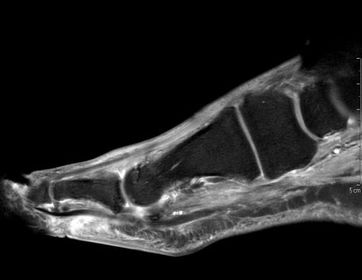

What does this indicate? | Increased signal and enhancement of the soft tissue plantar to the proximal phalanx suggestive of subcutaneous infection without abscess |

What does this indicate? | Increased signal and soft tissue distension dorsally representing subcutaneous abscess communicating with associated with plantar ulcerative defect. |